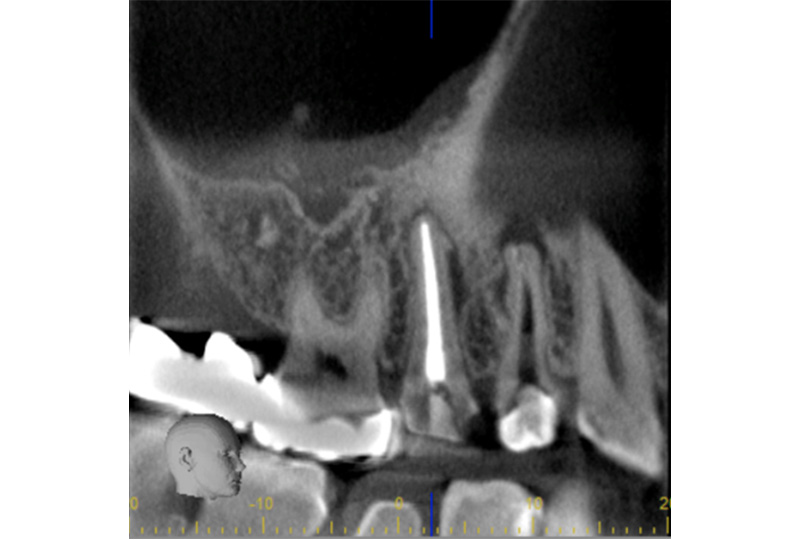

『歯のひび(歯根破折)』など通常であれば抜歯と言われるような歯の保存や歯を失った所に親知らずなどを移動させる『歯の移植』など一般の歯科医院では行わない特殊な治療も行なっております。